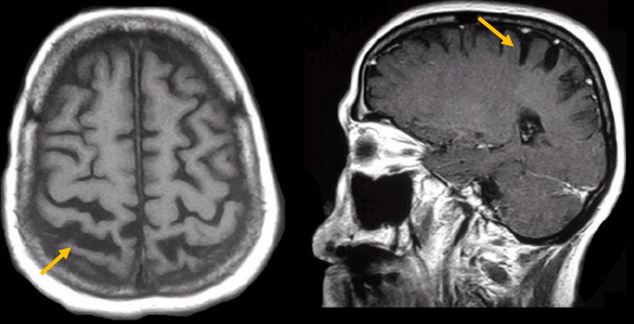

진행 핵상 마비는 대표적인 파킨슨 증후군 중의 하나입니다. 파킨슨병과 다른 점은 질병의 초기부터 중심을 잡기 어려운 체위 불안정이 나타나 자주 넘어진다는 것입니다. 파킨슨병의 경우 질병이 상당히 진행된 뒤에 체위 불안정이 나타납니다. 또한 진행 핵상 마비에서는 목 주위 근육을 비롯한 몸 중심 근육의 경축이 나타나, 목을 뒤로 젖히면서 걷는 모습이 보입니다. 그리고 눈의 운동을 조절하는 기능에 장애가 나타나 아래쪽을 바라보는 데 문제가 생겨 계단을 내려갈 때 어려움을 겪는 경우가 많습니다. 진행 핵상 마비가 의심되는 경우, 뇌 자기공명영상(MRI)에서 중뇌의 위축이 비정상적으로 심하게 나타나는 소견을 확인하거나, 뇌포도당 양전자 단층촬영(PET)에서 전두엽과 중뇌의 대사 기능이 저하된 소견을 확인하여 진단에 참고할 수 있습니다.

[진행핵상마비 환자의 뇌자기공명영상에서 확인되는 중뇌 위축 소견]

[진행핵상마비 환자의 뇌포도당 양전자 단층 촬영에서 확인되는 중뇌의 대사 저하 소견]2. 다계통 위축(Multiple system atrophy)